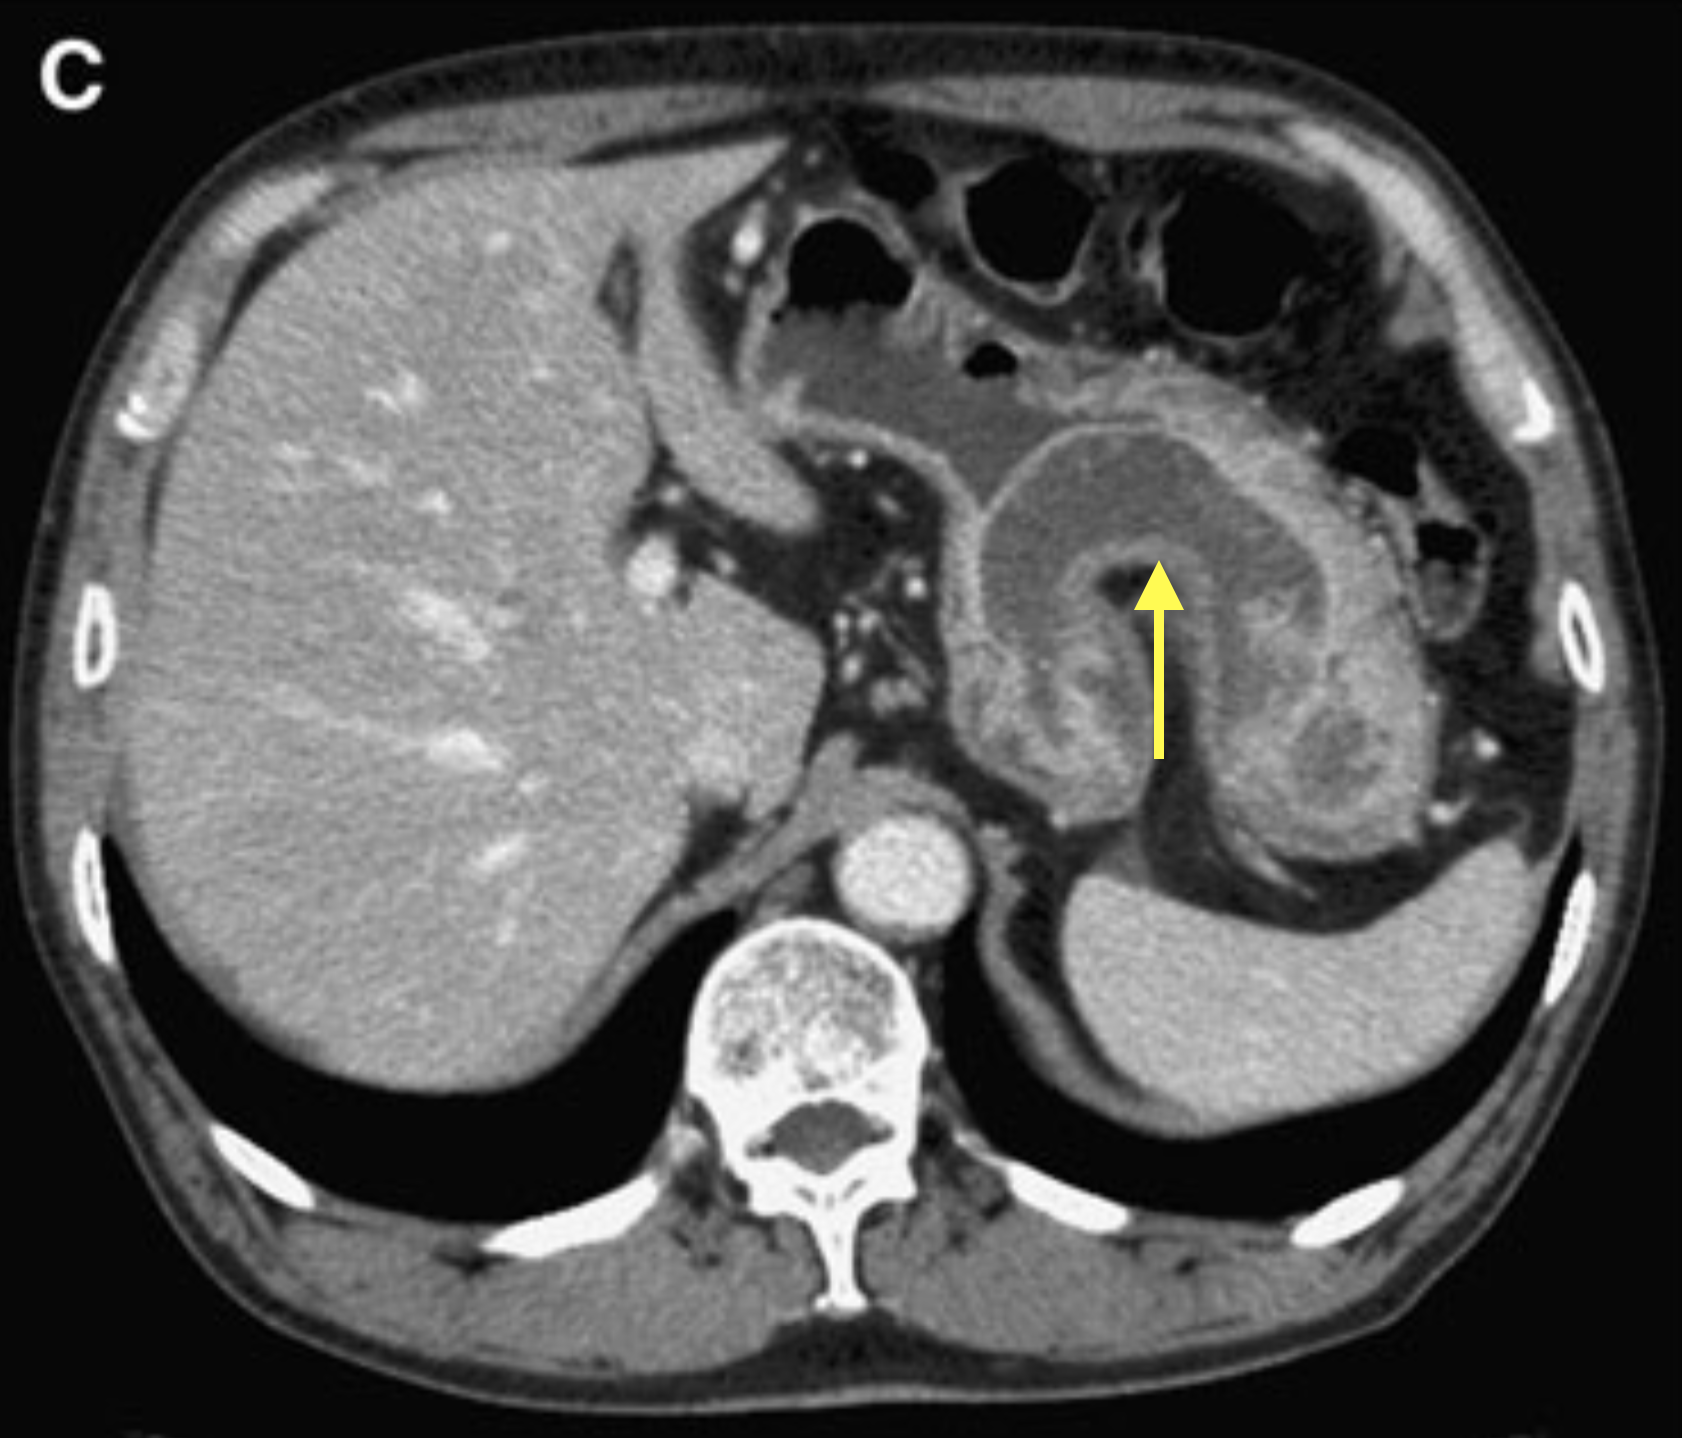

これらの他疾患と比較し、胃アニサキス症では胃の3層構造のうち2層以上の壁肥厚を認め、また肥厚した壁のCT値が低いことが特徴としてあげられます(図2)4)5)。

(図2:文献9より引用.造影CT門脈相.矢印:限局的な胃壁の肥厚)